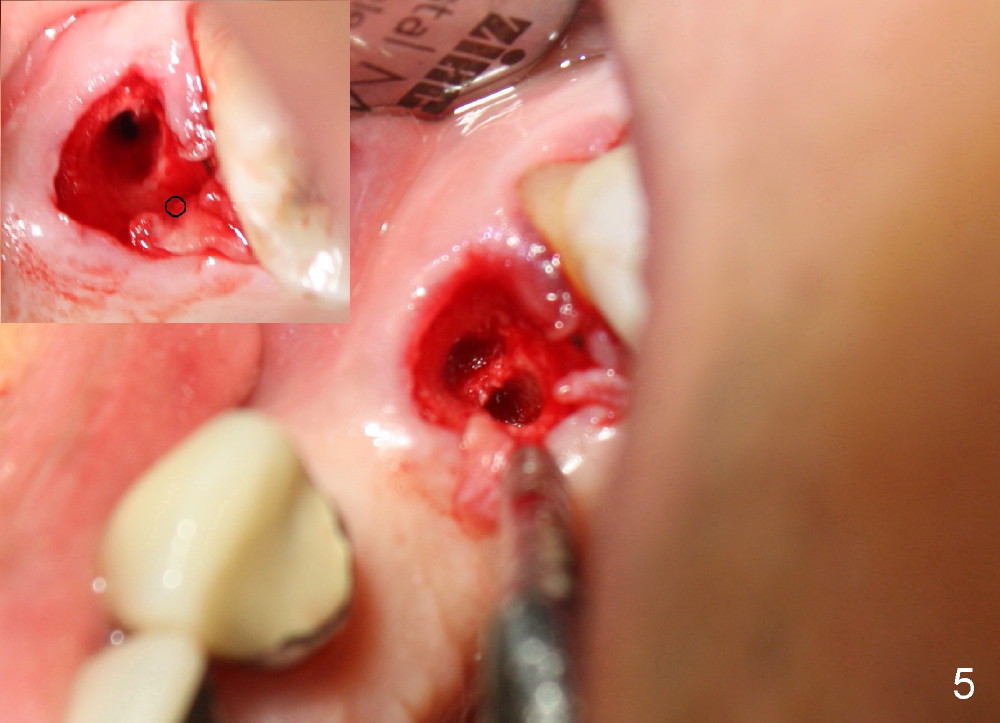

The anterior retainer is kept as a crown at #11 (Fig.2: C), whereas the residual root at the site of #13 is extracted with apical perforation (Fig.3 ^).  It is confirmed by Fig.4 (<).  To close the perforation, an osteotomy is initiated on the palatal wall of the socket with a 2 mm osteotome (Fig.5 insert: circle).  As the osteotomy is being enlarged by a 3 mm osteotome, the bone between the original socket and the osteotomy is being pushed buccally.  The former is being closed (Fig.5).  The osteotomy is finished with combination of osteotomes and reamers.  Fig.6 shows that a 5x14 mm tap is inserted at the site of #13 and that the sinus floor is lifted.  In fact the sinus membrane is partially torn at the osteotomy, which is repaired by insertion of Colla-form Dressing (Impladent), followed by autogenous bone (harvested from reamers) mixed with Osteogen  (Impladent).  A 5x14 mm implant is placed at the site of #13 with insertion torque more than 60 Ncm (Fig.7: I).  An incision is made at the site of #12 to start osteotomy with insertion of a parallel pin (Fig.7 P).  A 3 mm reamer is kept in place for position confirmation (Fig.8 R).  Due to ridge atrophy (Fig.2 arrowheads), a much smaller, but longer implant is placed at the site of #12 (Fig.9: 4x17 mm).  The autogenous bone harvested from #12 osteotomy is placed in the buccal gap of #13, followed by insertion of Colla-form Dressing (Fig.10 M).  To protect the membrane, a short abutment (4x3 mm) is temporarily placed (Fig.9,10 A) and perio dressing (Fig.9 D) is applied around the abutment and the interproximal areas of the neighboring teeth.  Usually perio dressing dislodges around 1 week postop, particularly for a large edentulous space.  In this case, the dressing is quite stable 11 days postop: the abutment (Fig.11 A) appears to contribute to retention of the dressing (D).